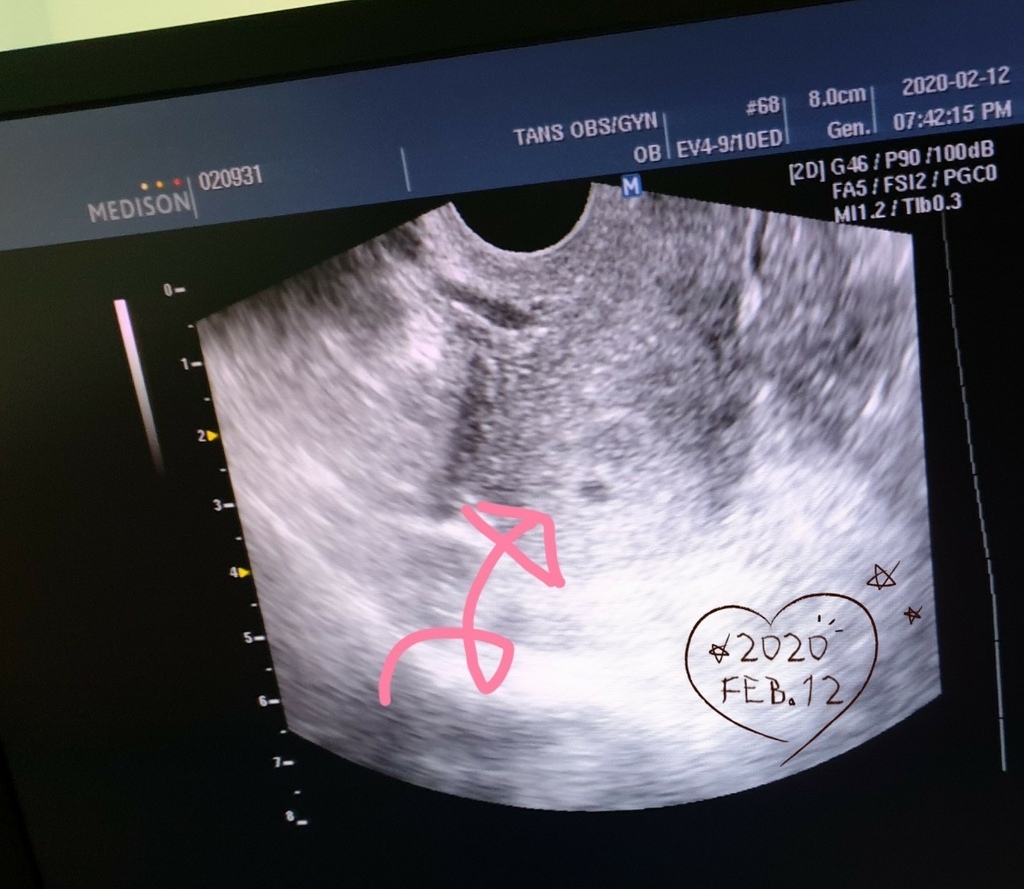

覺得應該很好懷孕的我,很快的在去年2020二月懷孕了

結果胚胎不健康,七週醫生打針讓他淘汰流出來

我上廁所掉出一點血塊,後來回診吃藥吃些中藥調身體,念心經

抱持著希望覺得在等等或許他還在長大,等到8週醫生說胚胎是空包彈跟我上次一樣

但由於有點過大,建議手術處理掉比較好,我做了引產手術...心情真的好差